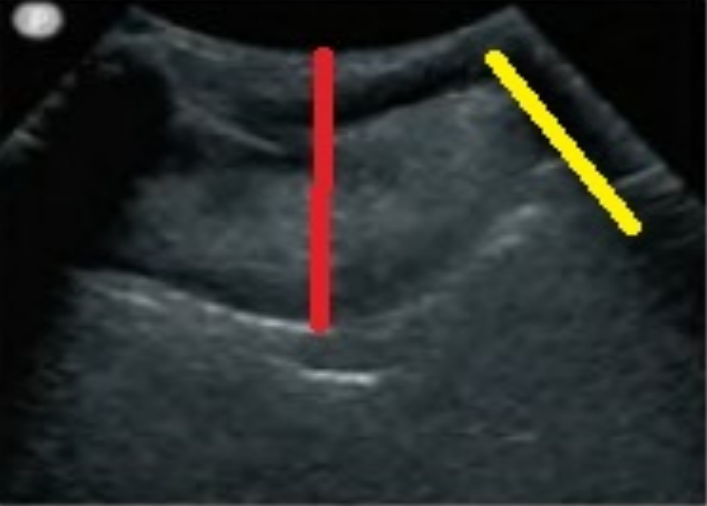

7. 食管平面的扫查

我们嘱患者头转向右侧,在胸骨上切记偏左的位置,以高频线阵探头做横向扫查,可以发现颈段食管的超声影像。图11中黄色区域为气管软骨环,蓝色区域为食管,红色区域为颈内动脉。

图片

图11  食管平面的扫查